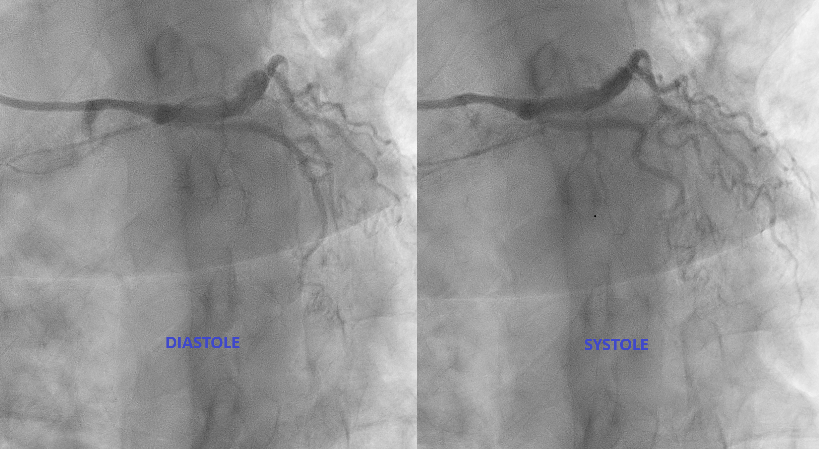

IVUS pullback performed:

Dynamic compression of LMCA externally (MLA reduction by 47.3%, from 12.8 to 6.74 mm2)Minimal intimal plaqueLAD, LCX, RCA was normal.